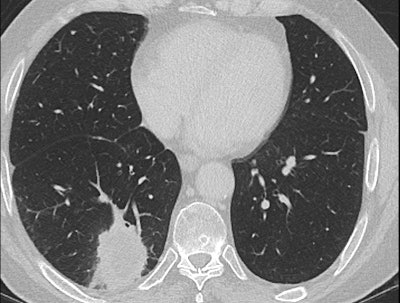

In her Liverpool talk, Strickland showed examples of missed lung cancers. In one case, leading to a duty of candour procedure, the lung bases, visible on a CT scan of the abdomen performed for suspected pancreatic pathology, had not been looked at on lung contrast windows, causing a small right basal lung cancer to be missed (see images above). On a subsequent chest CT scan several months later, the lesion was much bigger, and a second cancer was present in the left upper lobe. A duty of candour was issued because the lung cancer was at a higher stage when it was finally detected, likely leading to a worse outcome for the patient.

As we discussed in consultation this morning, I am very sorry that your CT scan undertaken to investigate pain in your abdomen and pancreas on Xth April 2014 did, in fact, show a small nodule in the bottom of the right lung. It is likely this was the early stage of the squamous cell cancer that we have now found in the right lung and are planning to treat.

A full and thorough investigation will be carried out by XXX Hospital as to why this small nodule was overlooked on the CT scan and why the scan was not flagged to the lung cancer team.

Again, I do apologize that this was missed, and I am very confident that we have a good plan for your treatment moving forward.